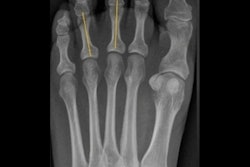

Asparagus finger. X-ray of finger, phalanx looks like an asparagus tip.